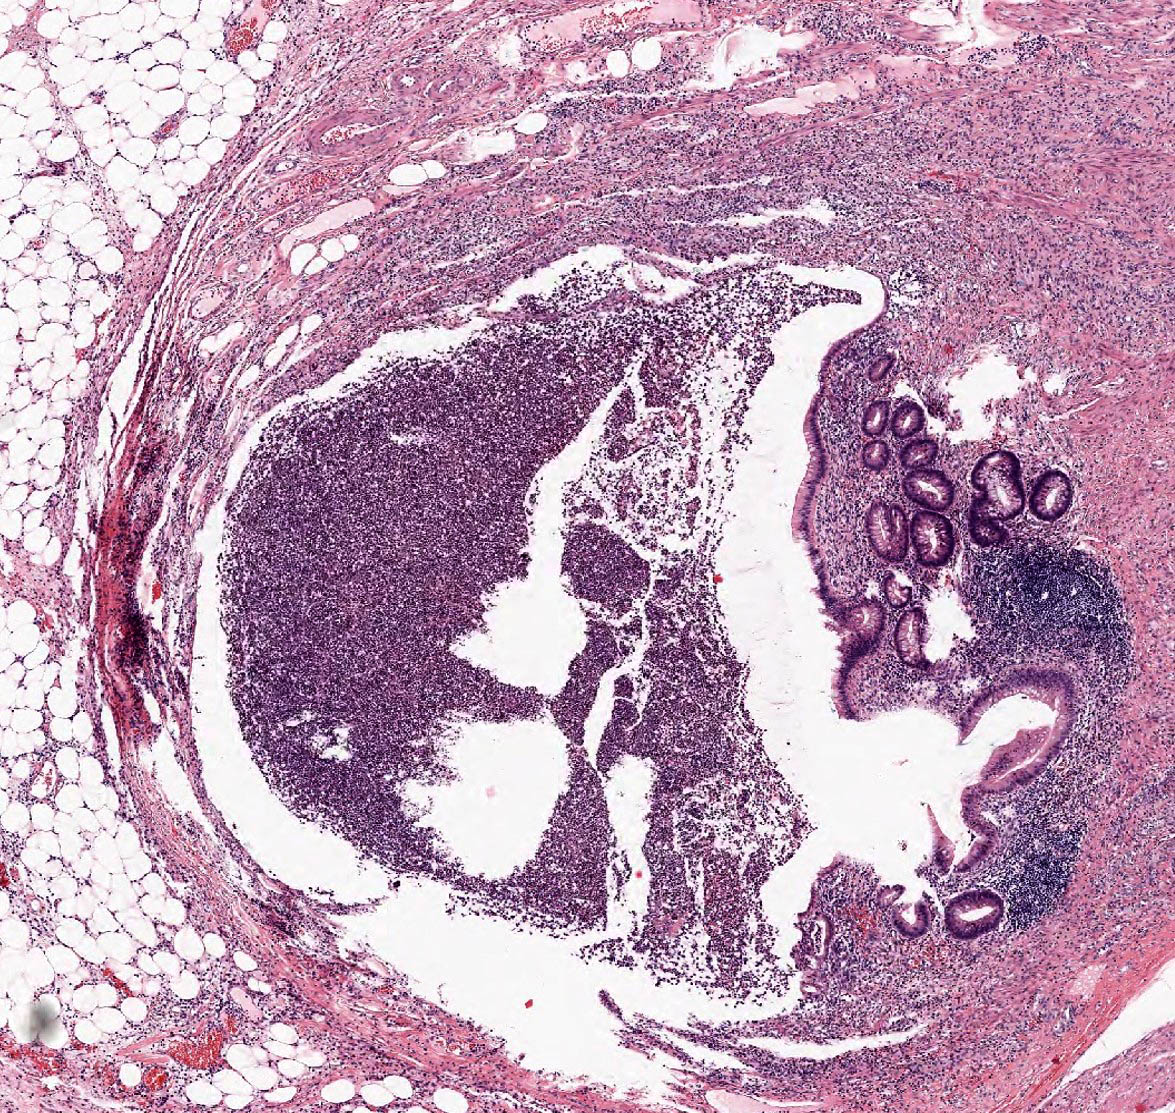

Microscopic (histologic) description

- Variable acute inflammation with predominance of neutrophils; involves some or all layers of the appendiceal wall

- Process may be divided into acute focal, acute suppurative, gangrenous and perforative

- Early lesions display mucosal erosions and scattered crypt abscesses

- Later, the inflammation extends into the lamina propria and collections of neutrophils are also seen in the lumen

- Mural necrosis in gangrenous appendicitis

- Process may be divided into acute focal, acute suppurative, gangrenous and perforative

Microscopic (histologic) images

A 40 year old caucasian man presented into the emergency room with right lower quadrant pain associated with vomiting, abdominal tenderness, fever and moderate leukocytosis. Acute appendicitis was suspected and he underwent an appendectomy. His appendix was sent to pathology for histological evaluation. The H&E images are shown above. Which of the following is the most likely diagnosis?

- Appendiceal diverticulitis

- Appendiceal endometriosis

- Interval appendicitis

- Low grade appendiceal mucinous neoplasm